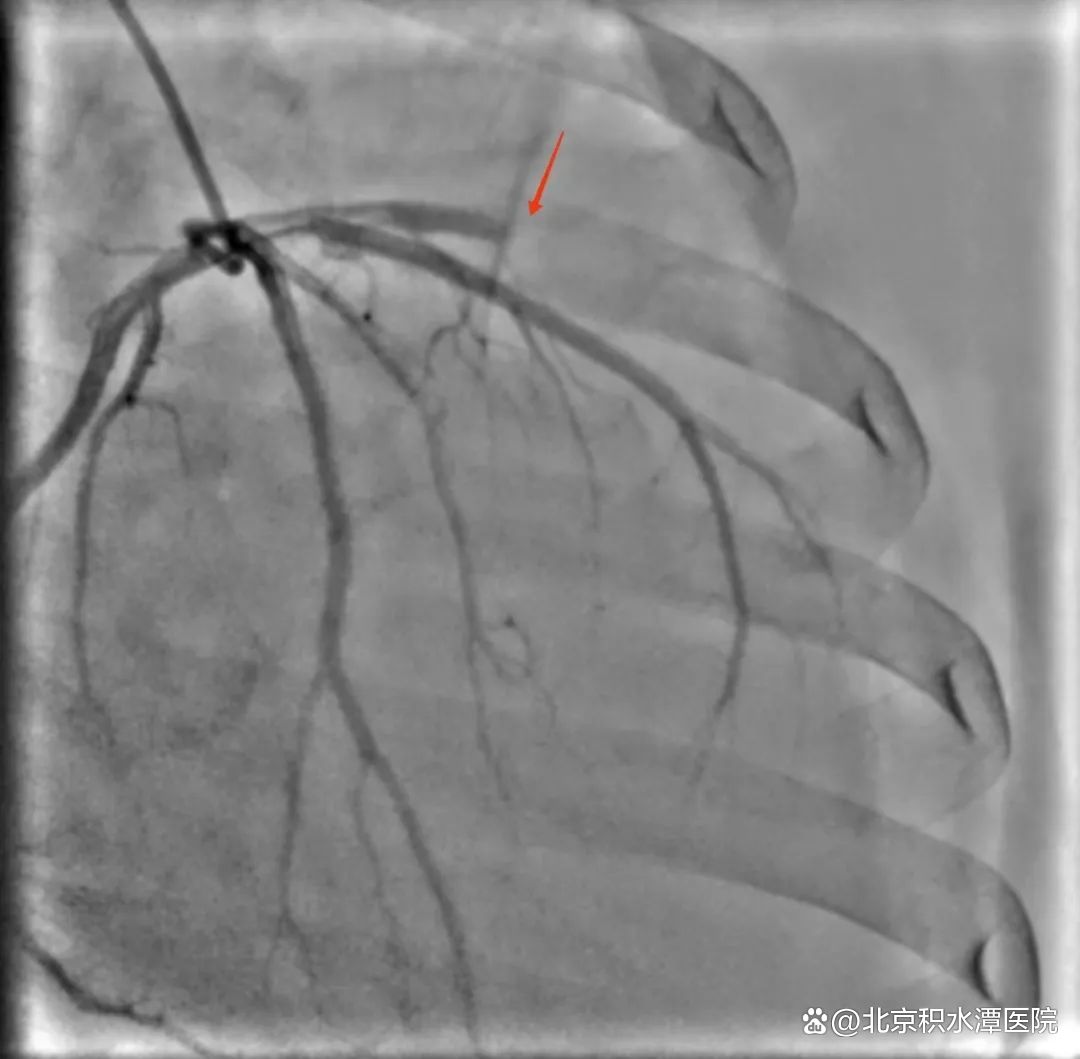

转运途中,患者突发室颤,经过医护人员除颤和抢救,患者才恢复意识。抵达新龙泽院区后,医院立即启动了急性心梗抢救团队,专家们进行了紧急会诊和手术准备工作,患者被紧急送往导管室,通过急诊介入手术(PCI)进行了血管再通。手术过程中,由于再灌注损伤,术中心脏室颤再次发作,医生们沉着冷静进行除颤和抢救,心律稳定后,成功地为患者疏通了被堵塞的血管,改善了心肌缺血现象,挽救了患者生命。